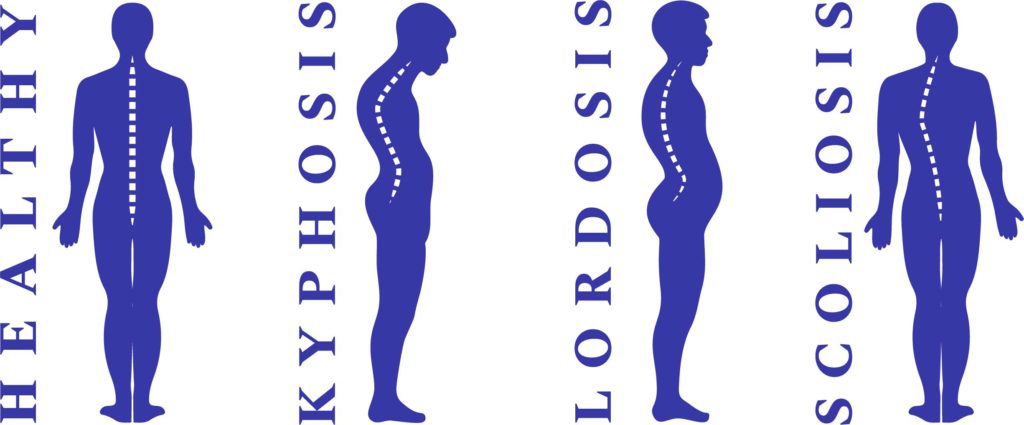

Spinal Curvature Pathology

The image depicts four silhouettes representing different spinal curvatures in the sagittal and coronal planes.

The first silhouette, labeled “Healthy,” shows a normal spine with a gentle kyphotic curve in the thoracic region (upper back) and a lordotic curve in the lumbar region (lower back). This is considered the ideal spinal alignment, providing balance and allowing for efficient movement and shock absorption.

The second silhouette, labeled “Kyphosis,” demonstrates an exaggerated outward curve of the thoracic spine. This condition can lead to a hunched-back appearance and is often associated with osteoporosis or degenerative spine diseases.

The third silhouette, labeled “Lordosis,” shows an increased inward curvature of the lumbar spine. Commonly referred to as “swayback,” it can create significant lower back pain due to the added stress on the lumbar spine.

The fourth silhouette, labeled “Scoliosis,” illustrates a lateral, or sideways, curvature of the spine. Unlike the other conditions, scoliosis affects the spine in the coronal plane and can lead to an asymmetrical appearance of the back and shoulders.

Overall, these silhouettes serve as a visual reference for understanding common spinal deformities and their differences from the normal spinal curvature.